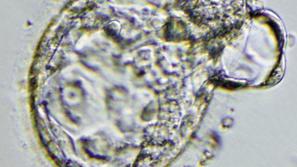

Embrio v zgodnji fazi

Svet

Znanstvenikom uspel veliki preboj

Prvič v zgodovini je znanstvenikom uspelo klonirati človeški embrio, iz katerega so lahko pridobili zdrave izvorne celi…